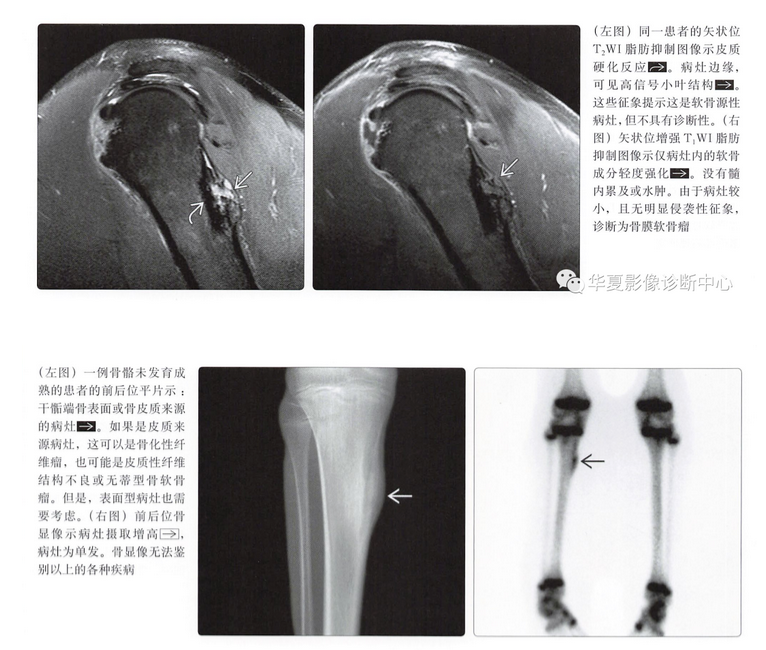

MR表现

- 病灶的结节状形态

- T1上等或低信号

- T2上高信号

- 不均匀强化,通常呈边缘强化

- 髓内累及(20%)

- 髓内水肿(20%)

- 不规则软组织肿块(30%)

骨膜软骨肉瘤

- 很少见的表面型软骨肉瘤

- 通常为低度恶性,因此可能不会出现明显侵袭性

- 几乎与骨膜软骨瘤影像表现相同

- 类似的MR特征

- 低级别软骨形成小叶结构,液体敏感序列上呈高信号

- 边缘强化,伴比较小的软组织肿块

- 与骨膜软骨瘤没有可靠的鉴别点,但是

- 病灶可能比大多数骨膜软骨瘤大